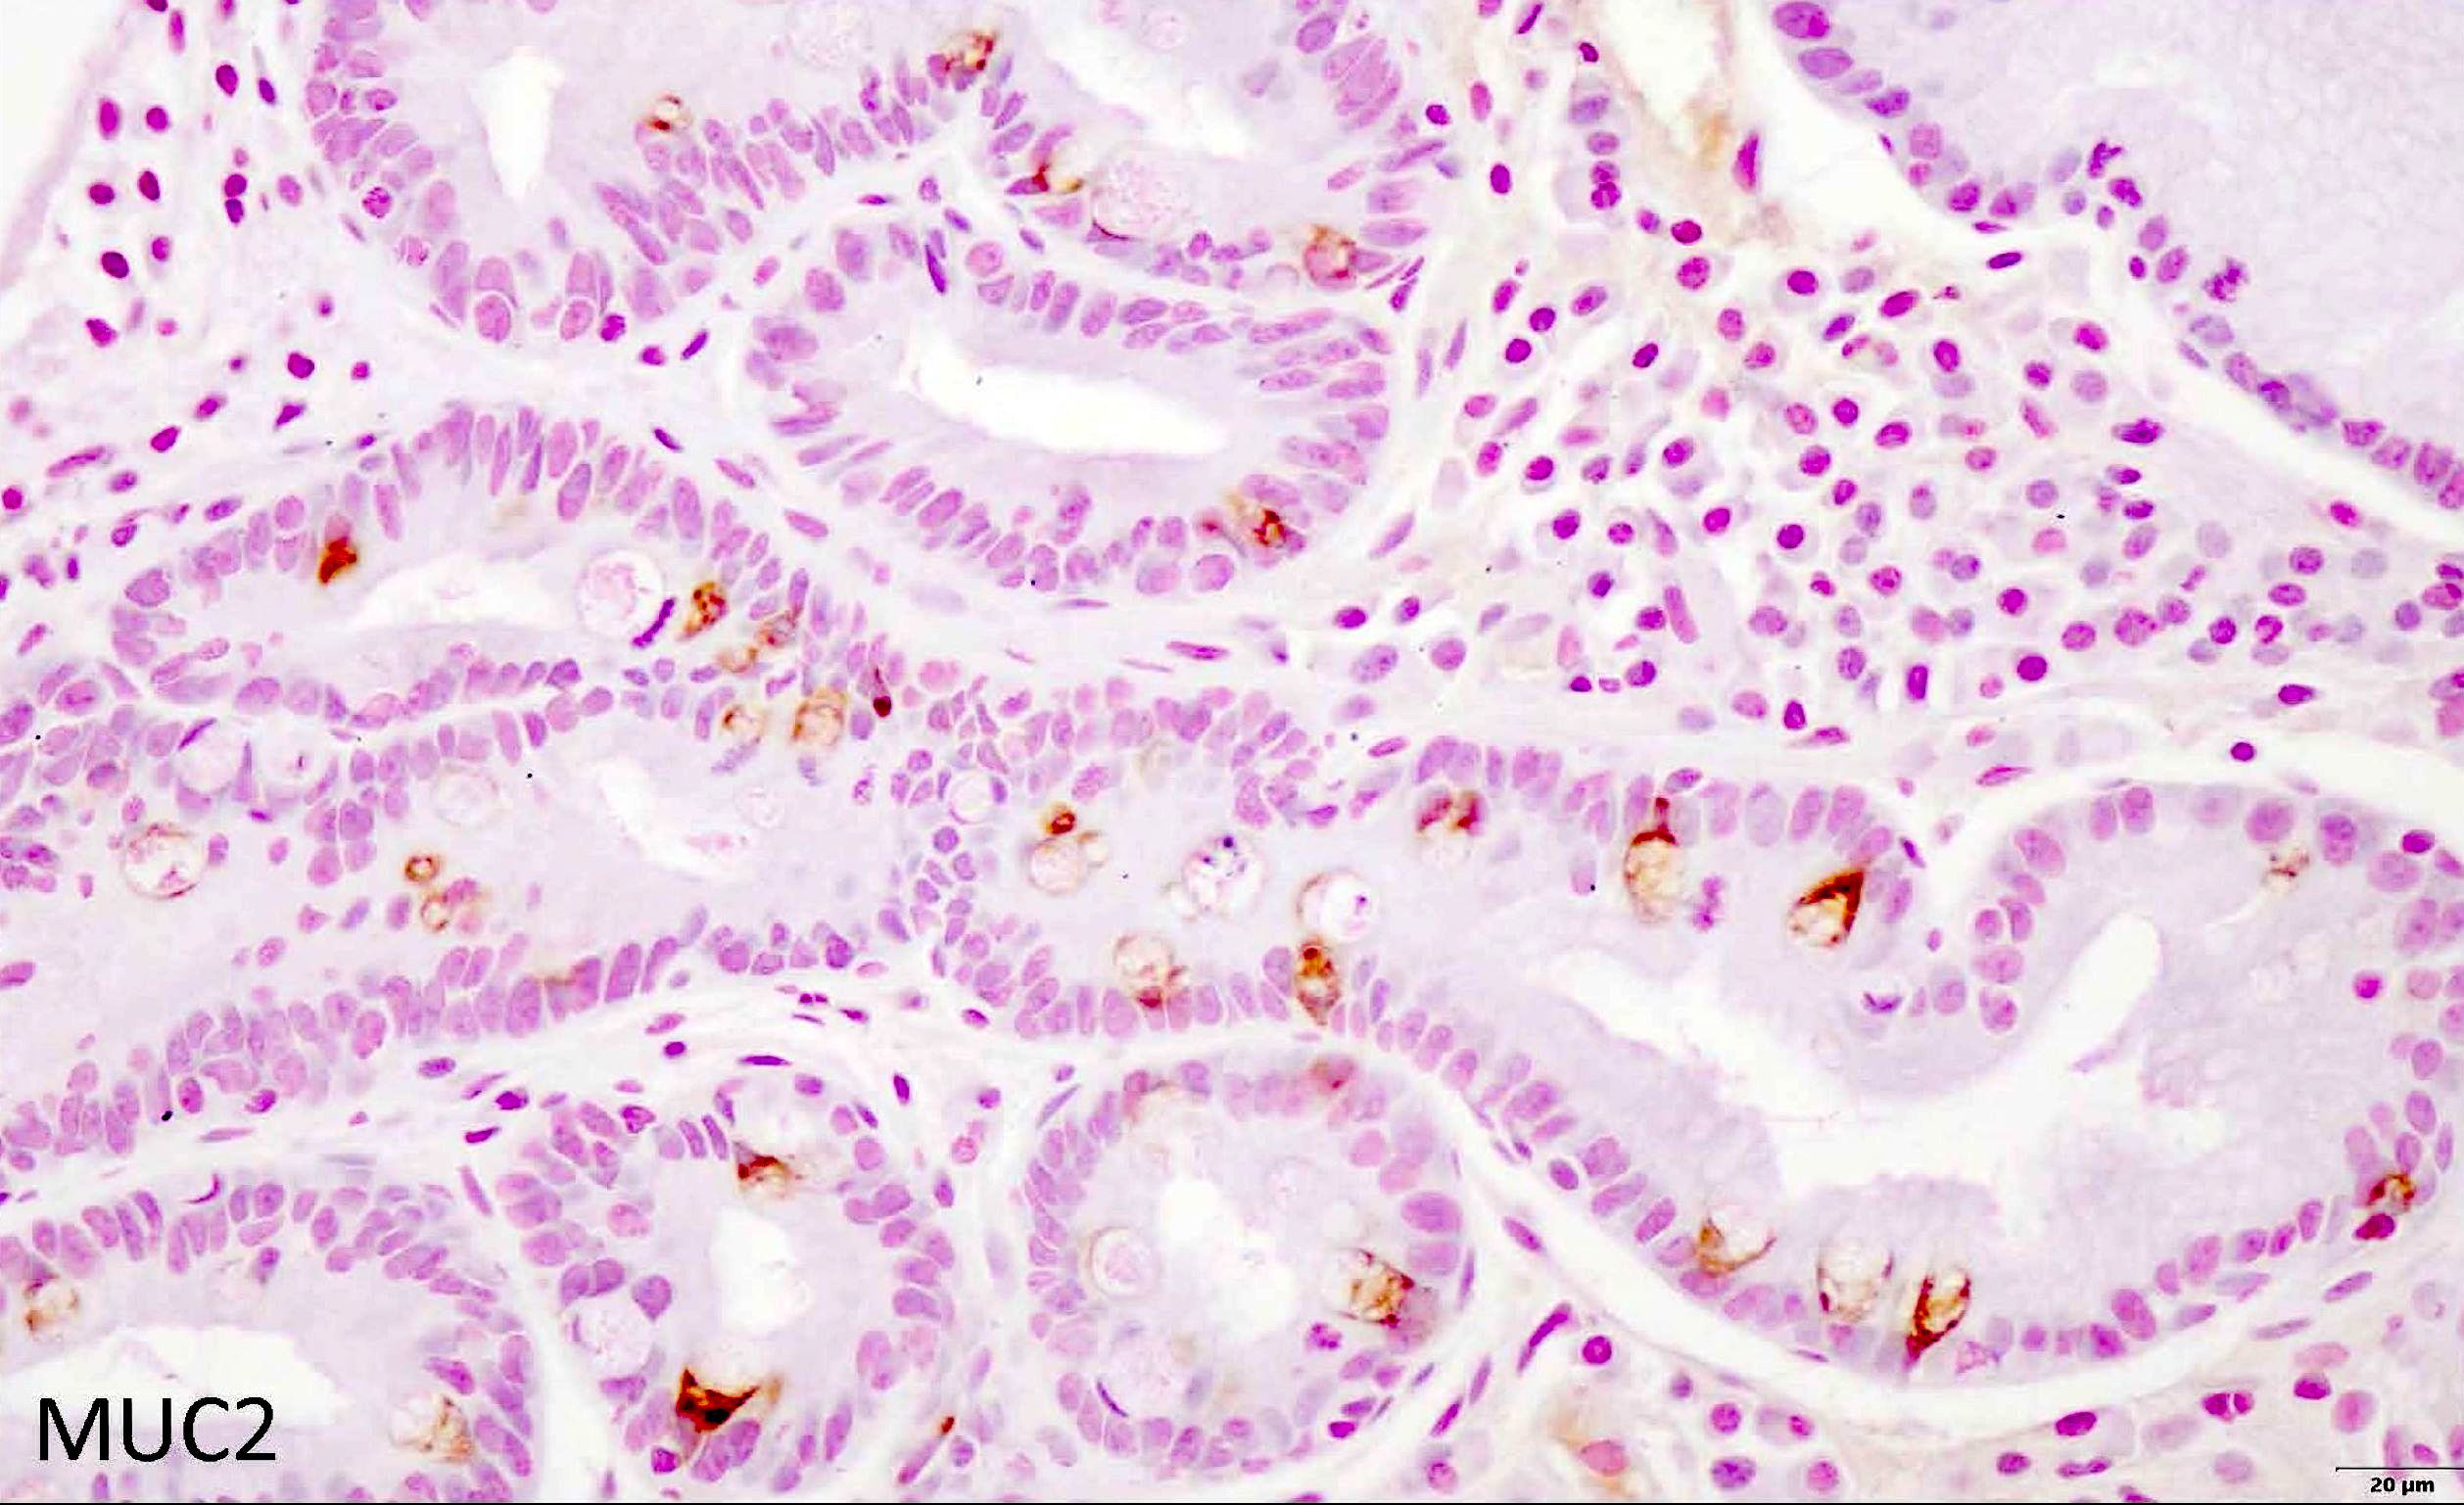

Positive stains

- MUC2 IHC: de novo expression in the cytoplasm of goblet cells (Virchows Arch 2002;440:311)